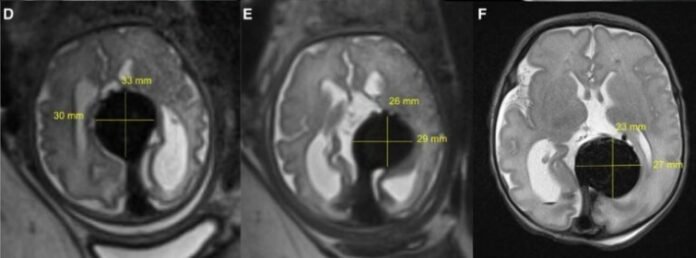

Ненароджений малюк мав судинну аномалію – ваду розвитку вени Галена, однієї з великих кровоносних судин черепа, що загрожує смертельними ускладненнями після народження дитини.

Мальформація вени Галена зустрічається приблизно у 1 з 60 тисяч немовлят – це рідкісний тип судинної аномалії головного мозку, при якій артерії з’єднуються безпосередньо з венами, а не з капілярами, які мали б контролювати потік крові.

Потік крові у вені занадто швидкий – захворювання створює значне навантаження на серцево-судинну систему, що може призвести до серцевої недостатності.

Також це може спричинити гіпертензію в артеріях легень і серця, а через додатковий тиск у головному мозку – значне пошкодження мозку, неврологічні та когнітивні порушення і навіть смерть.

“Першим пацієнтом” став плід на 34-му тижні вагітності жінки – вони використовували ультразвук для проведення процедури емболізації.